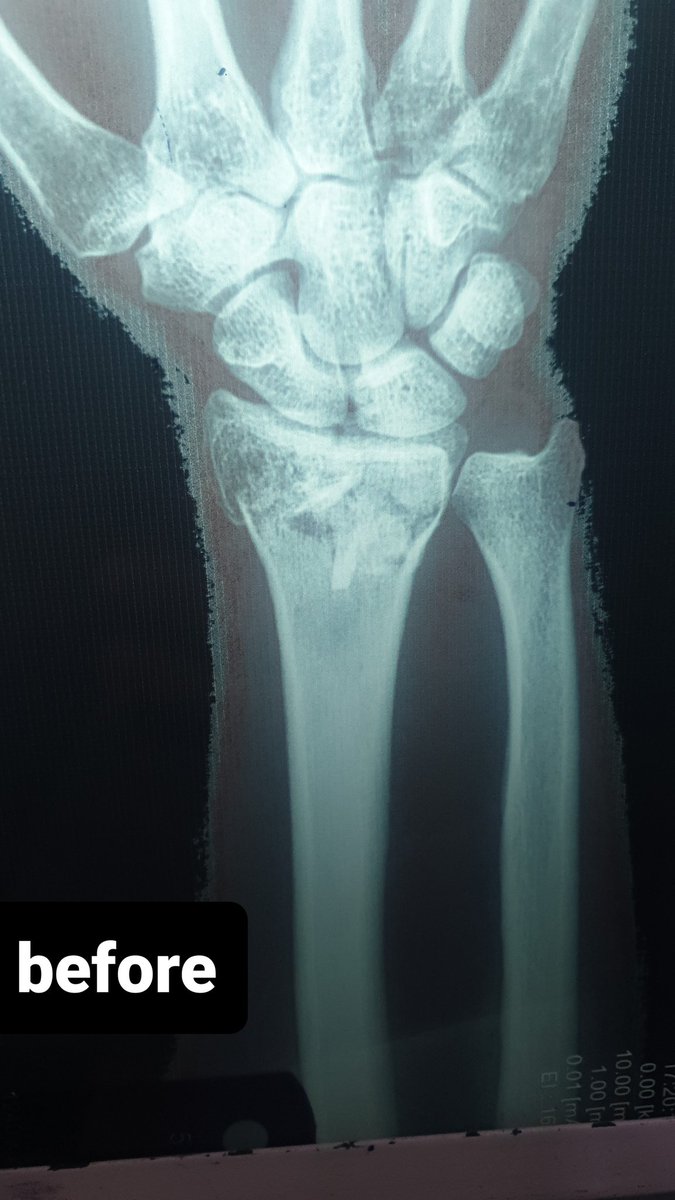

58 male fall from height last week !

Hx: HTN , CAD

Medicine :Aspirin 81 , Clopidogrel

When I aspirate hematoma there was about 6 ml blood

this is the pre_after reduction and the follow up today

He is not elderly in shape and body he looks like 40 !

1/2